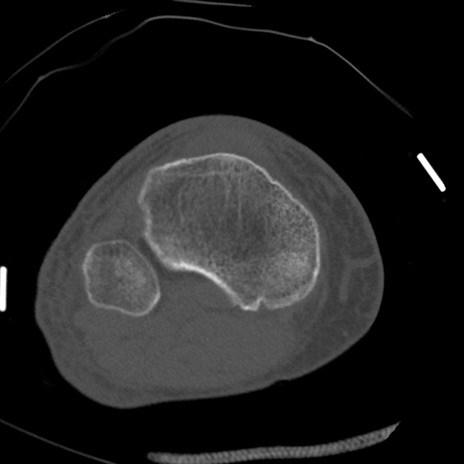

症例28 右膝関節CT(横断像)

右膝関節CT